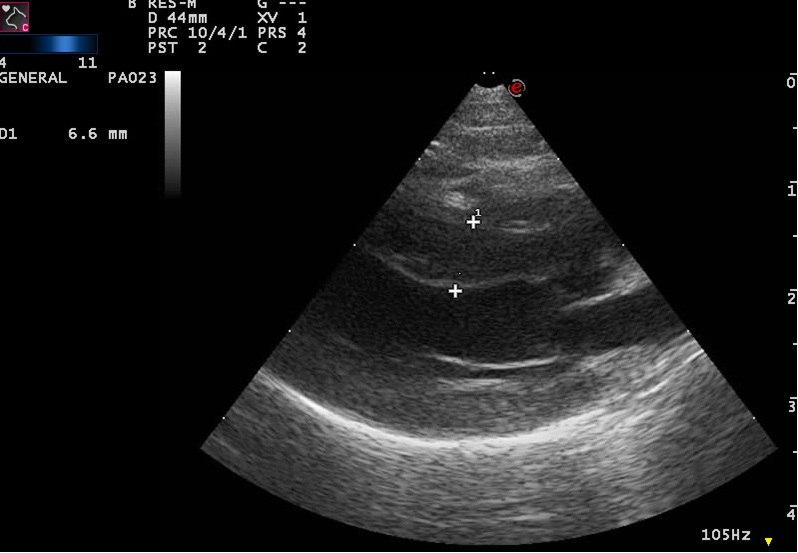

Основы эхокардиографии в пропедевтике внутренних болезней: Иллюстрации и примеры